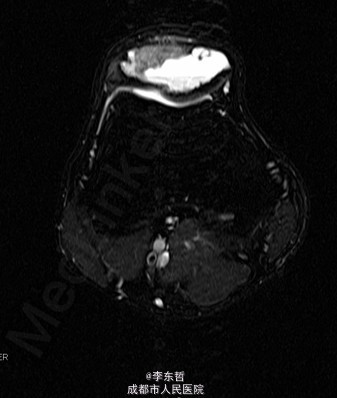

查体:视:右侧膝关节未见明显肿胀,皮肤无破溃,无血管怒张。触:右侧髌骨上方有压痛明显,皮温较对侧不高,浮髌试验阴性,肢体末端血供、皮肤感觉未见异常。动量:右侧膝关节主动活动无明显异常,肌力5级,肢体长度正常。入院前后完善相关检查:SPECT骨动态显像示:右侧膝关节区骨代谢增高;右膝关节X线示:右髌骨形态欠规则,其内多发低密度囊状影,性质?。MRI膝关节普通扫描提示:右膝髌骨改变,考虑骨囊肿或其它?。输血或术前全套示:HBSAG(+)、HBEAB(+)、HBCAB(+)。

患者在全麻下行“右髌骨肿瘤病灶刮除活检、病腔灭活、取自体髂骨植骨、张力带钢丝内固定术”。术中见:右侧髌骨内可见暗褐色血肉样、纤维样混杂组织,质脆,囊内有少量清亮积液,囊腔大小约为4cm×3cm,局部骨质有侵蚀。术后病检结果回示:(右髌骨)软骨母细胞瘤。术后复查膝关节X线及CT提示:右髌骨内固定器在位,未见松脱及断裂。